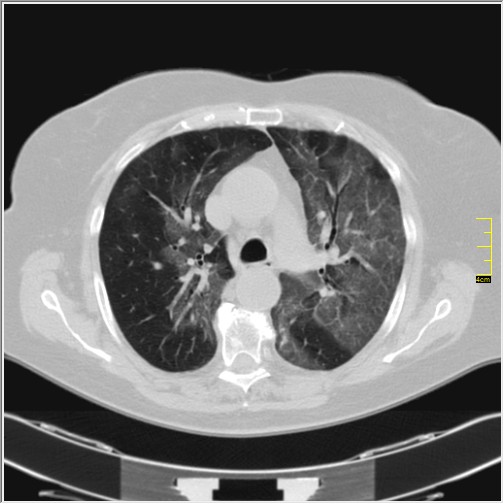

Foto: Aleksandar Ivković Foto: Aleksandar Ivković Foto: Aleksandar Ivković Strašna razlika kod pluća pušača i kovid pozitivne osobe autor: Božica Luković Zdravlje 23. jan. 2021. 12:06 > 23. jan. 2021. 12:15 0 Podeli vest: Radiolog Aleksandar Ivković od početka pandemije daje korisne informacije o svim aspektima kovida 19. On je nedavno uporedio rendgen snimke pluća zdrave osobe, pušača, osobe koja je zaražena gripom H1N1, a onda i osobe koja ima kovid 19. Razlike su zapanjujuće. Podeli vest: Oglas Objavu doktora Ivkovića sa njegovog bloga "Ljudi i ostale laži" prenosimo u celosti."Nedavno sam video u medijima da je neko preneo rdg sliku i razlike kod nalaza zdrave osobe, pušača i bolesnog od kovida 19. Kako nisam baš previše zadovoljan onim što je prikazano, evo kako to izgleda u našoj varijanti. Zdrava osoba CT nalaz kod zdrave osobe podrazumeva da ne postoje nikakvi poremećaji strukture plućnog parenhima, da su krvni sudovi uredni i da nema suženja disajnih puteva, kao i da nema uvećanih limfnih žlezda u hilusima pluća i medijastinumu. Foto: Aleksandar Ivković | Foto: Aleksandar Ivković * Foto: Aleksandar Ivković | Foto: Aleksandar Ivković Zdrava muška osoba mesec dana nakon zapaljenja pluća tokom kovida 19. Nalaz bez nekih posebnih problema iako se naziru tragovi zapaljenja. Snimak u boji je zdrava osoba, nepušač, bez ikakvih bolesti pluća u istoriji. Grip H1N1 Pokazaću samo drastične nalaze kod gripa H1N1, to je znači onaj grip koji je izazvao epidemiju španske groznice i epidemiju 2009. godine koja još uvek nije prestala (svake godine imamo makar 15%). Foto: Aleksandar Ivković | Foto: Aleksandar Ivković * Foto: Aleksandar Ivković | Foto: Aleksandar Ivković * Foto: Aleksandar Ivković | Foto: Aleksandar Ivković * Foto: Aleksandar Ivković | Foto: Aleksandar Ivković Nisu svi pacijenti imali ovakve nalaze, pokazujem one koji su imali tešku kliničku sliku. Kod gripa se sve odvija obično u sedam dana. Kao što se vidi, zapaljenje je bilo jednostrano, uglavnom. Ali kada je dolazilo do pogoršanja, onda je centralno obostrano dolazilo do edema pluća. Pušenje Kod pušača postoje razne varijante nalaza na plućima. U principu nisu tako dramatične kao što su zapaljenja. Nalaz na plućima kod pušača može biti potpuno normalan. Ovo ne pišem zato što podržavam pušenje, naprotiv, veliki sam protivnik, ali iznošenje laži nikada nije dobro. Dve dijagnoze su bitne kao posledica pušenja. Prva je hronična plućna opstruktivna bolest: Foto: Aleksandar Ivković | Foto: Aleksandar Ivković * Foto: Aleksandar Ivković | Foto: Aleksandar Ivković * Foto: Aleksandar Ivković | Foto: Aleksandar Ivković Jasna je razlika u nalazu, posebno na ovim slikama u boji, gde su ta plava polja delovi pluća koji su propali zbog cigareta (može da se uporedi sa zdravim plućima iznad).Druga bolest koja je česta kod pušača je u svakom slučaju karcinom. Foto: Aleksandar Ivković | Foto: Aleksandar Ivković * Foto: Aleksandar Ivković | Foto: Aleksandar Ivković * Foto: Aleksandar Ivković | Foto: Aleksandar Ivković * Foto: Aleksandar Ivković | Foto: Aleksandar Ivković Tkivo koje raste unutar pluća i razjeda ga. Takav je nalaz kod karcinoma pluća. Često je uzrok upotreba cigareta. Kovid 19 O kovidu sam pisao puno puta. Evo nekih slika, radi poređenja. Foto: Aleksandar Ivković | Foto: Aleksandar Ivković * Foto: Aleksandar Ivković | Foto: Aleksandar Ivković * Foto: Aleksandar Ivković | Foto: Aleksandar Ivković * Foto: Aleksandar Ivković | Foto: Aleksandar Ivković Nakon što pacijent bude izlečen od gripa ili kovida 19, pluća se mogu vratiti u normalu.To je razlika u odnosu na posledice upotrebe cigareta. Ovi snimci nisu postavljeni da bi se poredile bolesti, već da bi se ukazalo kako različite bolesti deluju na pluća. I ono što je veoma važno, ako neko dobije jednu od ovih bolesti, ne znači da u toku života neće dobiti drugu.Ne pišem zato smo smatram da sam najpametniji ili najpozvaniji da objašnjavam, nisam kao neki pojedinci ubeđen da samo ja imam znanje i istinu, pišem jer drugi ćute. Pišem jer ima i puno onih koji iznose laži, mora se tome stati na put.A ovi, koji pišu da sam umro, da sam oboleo od karcinoma, ovi koji mi žele da nađem dobro grobno mesto, šta da vam kažem, vi ste mi inspiracija. Svesni ste da sam u pravu i odlično znam da ste već uradili sve da se vakcinišete i mnogi od vas će to uraditi pre mene ali i dalje ćete ubeđivati druge da se ne vakcinišu i da je dobro za njih da se razbole i umru. Ima puno reči za vas u svim našim slovenskim jezicima, znate vi sami šta ste", piše dr Ivković.***Bonus video:https://youtu.be/MWucTT0qBsIPratite nas i na društvenim mrežama:FacebookTwitterInstagram Dr Lukić otkrio spisak svih antibiotika za kovid upalu pluća Zdravlje 0 Dr Žujović: Kako oporaviti pluća posle korone Zdravlje 0 Pet znakova da ti je kovid zahvatio pluća Zdravlje 0 Virusolog Ana Banko ruši veliku zabludu o ruskoj vakcini Emisije 0 aleksandar ivković korona kovid pluća snimak pluća Pratite nas na društvenim mrežama: Koje je tvoje mišljenje o ovoj temi? Učestvuj u diskusiji ili pročitaj komentare Budite prvi koji će ostaviti komentar Pošalji komentar Pročitaj komentare (0)